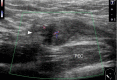

Inguinal hernia is the most prevalent type of abdominal wall hernia. Indirect inguinal hernia is twice as common as direct inguinal hernia. Computed tomography and magnetic resonance imaging can be used to evaluate inguinal hernia, but these modalities are greatly limited by their cost and availability. Ultrasonography has emerged as the most convenient imaging tool for diagnosing inguinal hernia due to its advantages, such as portability and absence of radiation. The present pictorial review presents an overview on the use of ultrasonography in the evaluation of inguinal hernia with a particular emphasis on the regional anatomy, relevant scanning tips, identification of subtypes, postoperative follow-up, and diagnosis of pathologies mimicking inguinal hernia.